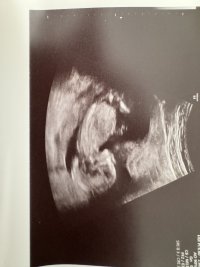

Kan se ut som jente, men veldig vanskelig å se på bildeneNoen som vil gjette kjønn? Uke 14+2